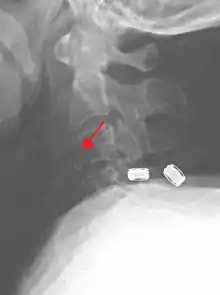

| A fracture of the base of the dens (a part of C2) as seen on CT. | |

On CT scan or X-ray, a cervical fracture may be directly visualized. In addition, indirect signs of injury by the vertebral column are incongruities of the vertebral lines,[7] and/or increased thickness of the prevertebral space:[8]

X-ray of normal congruous vertebral lines